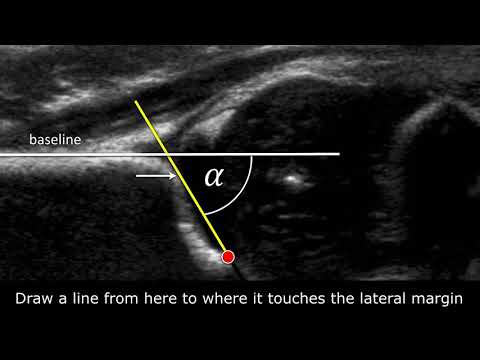

Congenital Hipdysplasia - How to measure angles